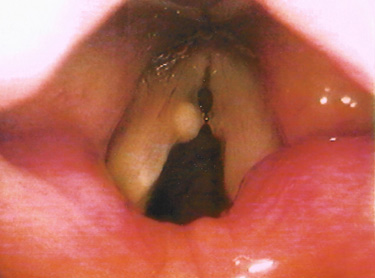

성대낭종은 과도한 음성사용으로 인해 주머니 형태의 양성종양이

점막아래에 형성된 것으로 성대점막의 면을 따라 둥근 공 모양으로 나타나는

표피양낭종과 점액을 분비하는 점액선의 관이 막혀서 생기는

저류낭종으로 분류할 수 있습니다.

표피양낭종은 성대에서의 돌출이 미미하고

저류낭종은 성대점막직하방에서 발생하여

후두 내부로 돌출하는 양상을 띠게 됩니다.

성대낭종은 성대결절이나 성대폴립과 감별 진단하는 것이 중요합니다.